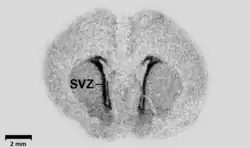

In biology, this technique may be used to determine the tissue (or cell) localization of a radioactive substance, either introduced into a metabolic pathway, bound to a receptor[4][5] or enzyme, or hybridized to a nucleic acid.[6] Applications for autoradiography are broad, ranging from biomedical to environmental sciences to industry.

The use of radiolabeled ligands to determine the tissue distributions of receptors is termed either in vivo or in vitro receptor autoradiography if the ligand is administered into the circulation (with subsequent tissue removal and sectioning) or applied to the tissue sections, respectively.[7] Once the receptor density is known, in vitro autoradiography can also be used to determine the anatomical distribution and affinity of a radiolabeled drug towards the receptor. For in vitro autoradiography, radioligand was directly applying on frozen tissue sections without administration to the subject. Thus it cannot follow the distribution, metabolism and degradation situation completely in the living body. But because target in the cryosections is widely exposed and can direct contact with radioligand, in vitro autoradiography is still a quick and easy method to screen drug candidates, PET and SPECT ligands. The ligands are generally labeled with 3H (tritium), 18F (fluorine-18), 11C (carbon-11) or 125I (radioiodine). Compare to in vitro, ex vivo autoradiography were performed after administration of radioligand in the body, which can decrease the artifacts and are closer to the inner environment.